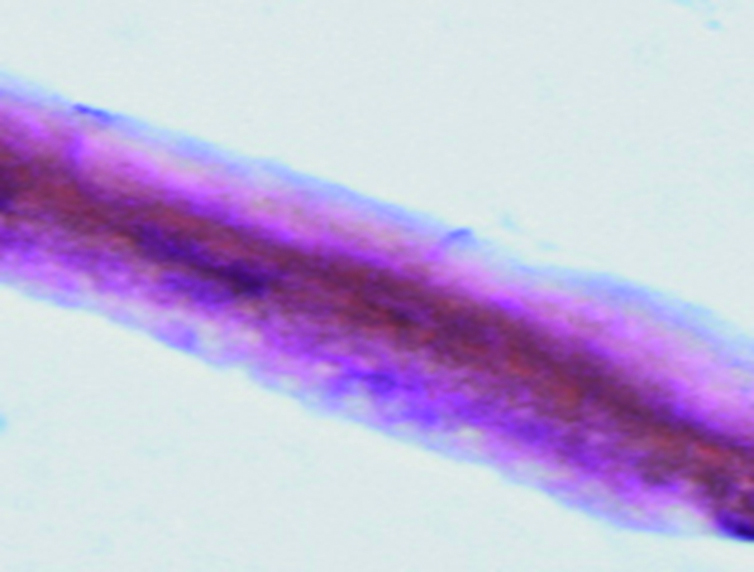

Scanning electron microscopy of preserved amniotic membrane samples from Group 3 revealed the following: the epithelial layer consists of minor cellular membrane fragments and the basement membrane that is desquamated across most of the examined surface. At higher magnification, the basement membrane appears as sparse fragments with curled edges, exposing the underlying stromal layer (Fig. 9).

Figure 9. Electron microscopic image of amniotic membrane in a scanning electron microscope. Epithelial surface of a lyophilized amniotic membrane preparation without preliminary impregnation with glycerol. Magnification x400.

Рисунок 9. Электронно-микроскопическое изображение амниотической мембраны в сканирующем электронном микроскопе. Эпителиальная поверхность препарата лиофилизированной амниотической мембраны без предварительного пропитывания глицерином. Ув. х400.